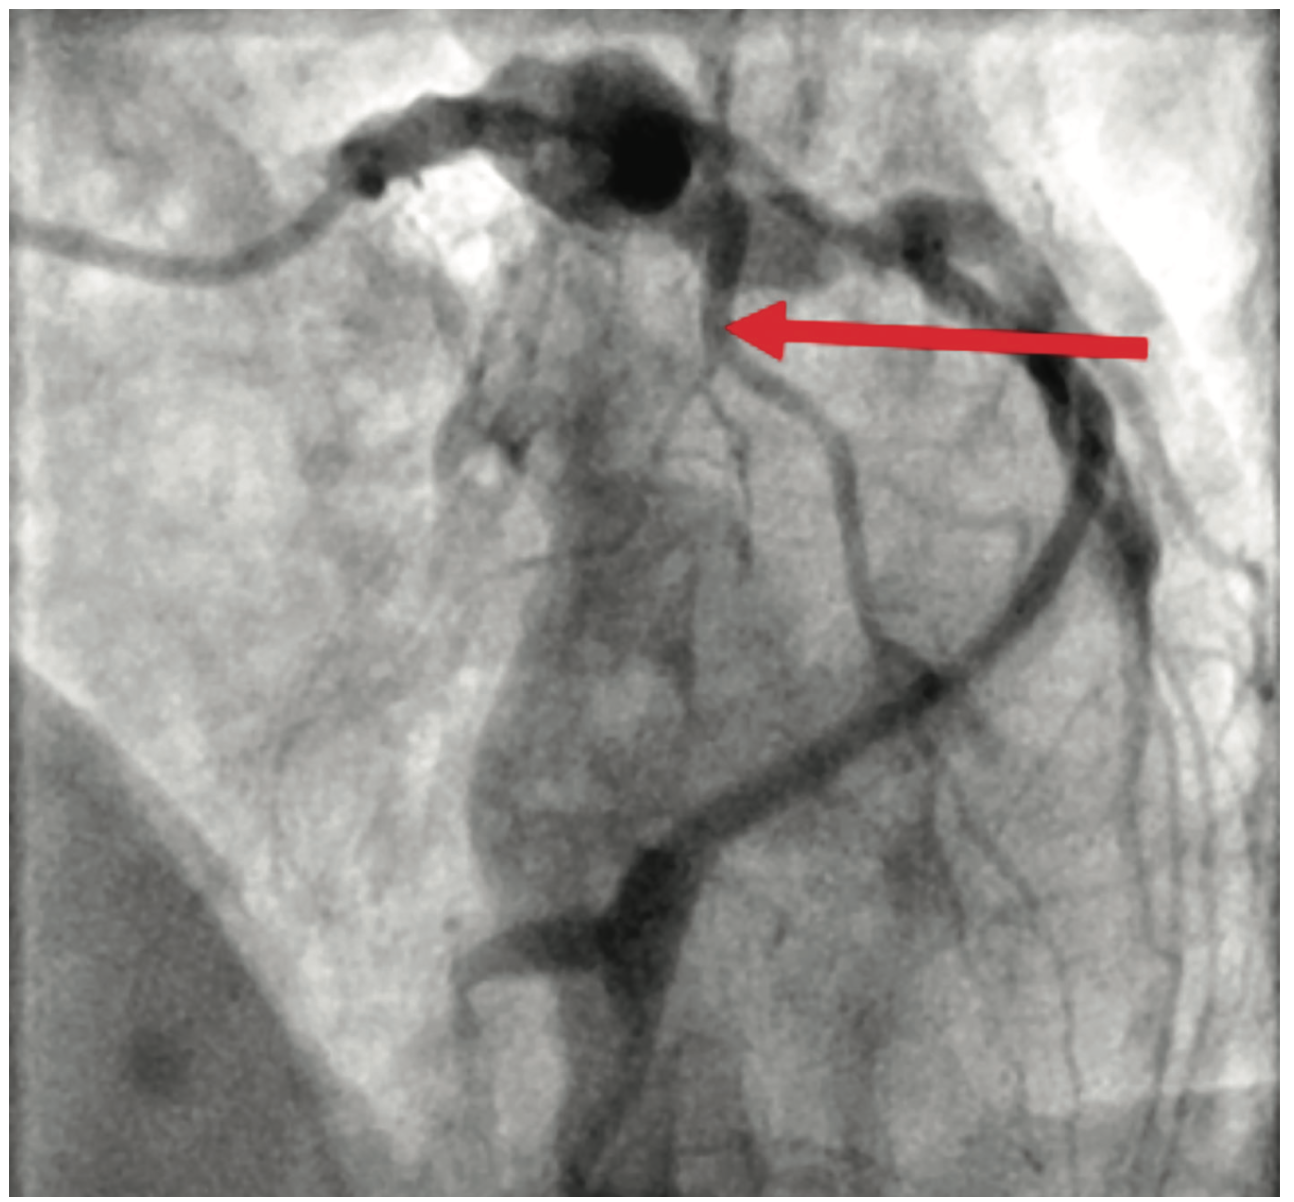

Figure 1. Occluded proximal LAD.

Cardiac catheterization showed total occlusion of the left anterior descending artery (LAD) with multiple coronary aneurysms in the LAD, left circumflex (LCx), and right coronary arteries. There was TIMI 0-1 slow flow within the coronary aneurysms. An eptifibatide bolus and drip was started. Aspiration thrombectomy using an Export catheter (Medtronic) and then rheolytic thrombectomy using an AngioJet catheter was performed on the proximal and mid LAD. A 4.0 x 16 mm bare metal stent was placed. However, the patient became hypotensive in the cath lab and a balloon pump was inserted. Prior to leaving the lab, there was resolution of the ST segment elevations. The patient was started on both a heparin drip and low-dose dopamine drip.